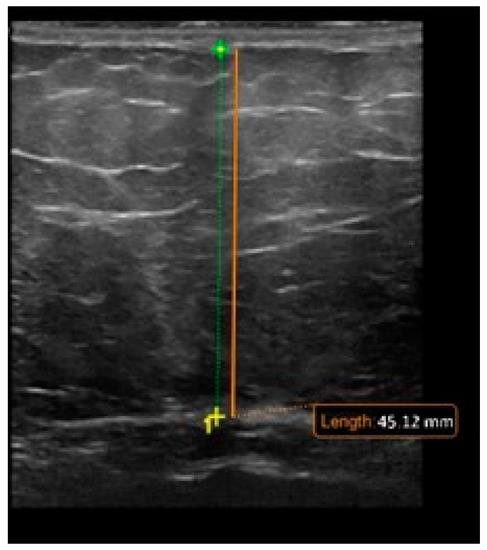

- De Lucia Rolfe, E.; Modi, N.; Uthaya, S.; Hughes, I.A.; Dunger, D.B.; Acerini, C.; Stolk, R.P.; Ong, K.K. Ultrasound estimates of visceral and subcutaneous-abdominal adipose tissues in infancy. J. Obes. 2013, 2013, 951954. [Google Scholar] [CrossRef] [PubMed]

- Wagner, D.R. Ultrasound as a tool to assess body fat. J. Obes. 2013, 2013, 280713. [Google Scholar] [CrossRef] [PubMed]

- Liem, E.; Rolfe, E.D.L.; L’abee, C.; Sauer, P.; Ong, K.; Stolk, R. Measuring abdominal adiposity in 6 to 7-year-old children. Eur. J. Clin. Nutr. 2009, 63, 835–841. [Google Scholar] [CrossRef]

- Koot, B.; Westerhout, R.; Bohte, A.; Vinke, S.; Pels Rijcken, T.; Nederveen, A.; Caan, M.; Baan-Slootweg, O.; Merkus, M.; Stoker, J. Ultrasonography is not more reliable than anthropometry for assessing visceral fat in obese children. Pediatr. Obes 2013, 9, 443–447. [Google Scholar] [CrossRef] [PubMed]

- Mook-Kanamori, D.O.; Holzhauer, S.; Hollestein, L.M.; Durmus, B.; Manniesing, R.; Koek, M.; Boehm, G.; Van der Beek, E.M.; Hofman, A.; Witteman, J.C. Abdominal fat in children measured by ultrasound and computed tomography. Ultrasound Med. Biol. 2009, 35, 1938–1946. [Google Scholar] [CrossRef] [PubMed]